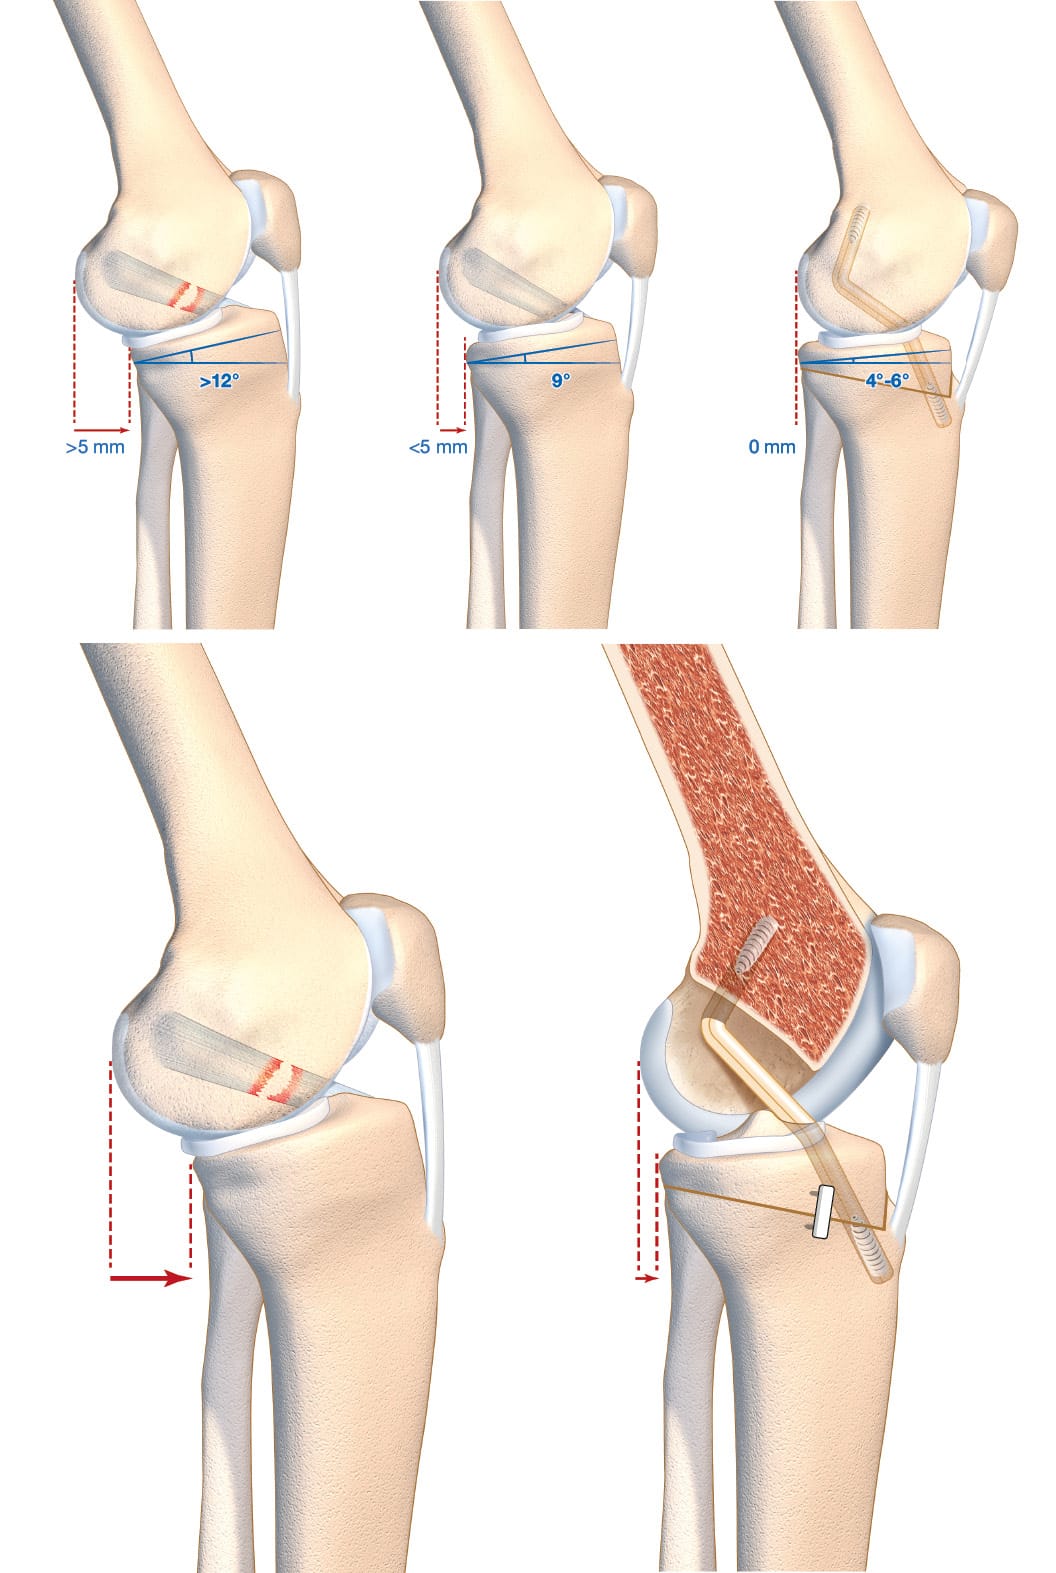

Radiology images should be obtained to include true lateral views showing 15 cm of proximal tibia with 20° of flexion in single-leg weight-bearing. The condyles will be aligned under fluoroscopy before the conventional radiography is performed. Any deviation from lateral will lead to distortions and the measurements will not be possible to interpret [14] Vieider RP, Mehl J, Rab P, Brunner M, Schulz P, Rupp MC, et al. Malrotated lateral knee radiographs do not allow for a proper assessment of medial or lateral posterior tibial slope. Knee Surg Sports Traumatol Arthrosc. 2024;32(6):1462–9. (Figure 1). Next, the technique for measuring the tibial slope must be chosen so that it is reproducible and can be compared from one study to another. It is crucial to choose one method and stick to it. The technique that uses the proximal anatomical tibial axis has a normal value of 9° of slope and the method is described in Figure 2 [15] Brazier J, Migaud H, Gougeon F, Cotten A, Fontaine C, Duquennoy A. Evaluation of methods for radiographic measurement of the tibial slope. A study of 83 healthy knees. Revue de chirurgie orthopédique et réparatrice de l’appareil moteur. 1996;82(3):195–200. . The normal value for SATT is 1.31 mm [16] Cance N, Dan MJ, Pineda T, Demey G, Dejour DH. Radiographic Investigation of Differences in Static Anterior Tibial Translation With Axial Load Between Isolated ACL Injury and Controls. Am J Sports Med. 2024 Feb 1;52(2):338–43. . If translation is posterior, the measurement will have a negative value. The measurement method is described in Figure 3.

Firstly, they may have an impact on the post-operative weight-bearing protocol. For example, patients with a tibial slope greater than 12° and/or a SATT greater than 5mm prior to surgery will begin with a non-weight-bearing phase lasting 21 days in order to decrease the stresses of excessive translation on the graft to protect it [17] Romandini I, Cance N, Dan MJ, Pineda T, Pairot de Fontenay B, Demey G, et al. A non-weight bearing protocol after ACL reconstruction improves static anterior tibial translation in patients with elevated slope and increased weight bearing tibial anterior translation. J EXP ORTOP. 2023 Dec 20;10(1):142. .

The intervention that directly addresses tibial slope is the tibial deflexion osteotomy (TDO) [18] Guarino A, Pineda T, Giovannetti de Sanctis E, van Rooij F, Saffarini M, Dejour D. The Original Technique for Tibial Deflexion Osteotomy During Revision Anterior Cruciate Ligament Reconstruction: Surgical Technique. Arthroscopy Techniques. 2024 Jan 1;13(1):102824. . This intervention was notably described by Dejour et al. in 1998, although it has been discussed at the Lyon Knee Surgery Congress since the early 1990s [19], Dejour D, Kuhn A, Dejour H. Osteotomie tibiale de déflexion et laxité chronique antérieure à propos de 22 cas. Rev Chir Orthop 1998 ; 84 SII : 28-29 [20] 7èmes journées lyonnaises de chirurgie du genou - Lyon 1991 [Internet]. [cited 2024 Aug 23]. Available from: http://lyon-knee-surgery.com/images/pdf/7%C3%A8mes%20journ%C3%A9es%20lyonnaises%20de%20chirurgie%20du%20genou%20-%20Lyon%201991/jdg-7/assets/basic-html/page-270.html. It is a sagittal realignment osteotomy. The technique described here is a supra-tubercular osteotomy (Figure 4). However, trans-tubercle and infra-tubercle strategies are also possible (Figure 5). This intervention is performed at the same time as the ACL reconstruction.

Indication: Repeat rupture and tibial slope ≥ 12° and a SATT ≥ 5mm. The number of surgical revisions and meniscal condition may lower these thresholds.

The procedure to choose to directly address posterior tibial slope is tibial deflexion osteotomy. It is possible to perform a supra-tubercular, trans-tubercle or infra-tubercle deflexion osteotomy, as described above (Figure 7). The most important factor in choosing a technique is that the surgeon feels at ease using it, since there is currently no technique emerging as superior to any other and each one has its own advantages and drawbacks [29] Onishi S, Kim Y, Nakayama H, Mansour AA, Lowe WR, Ollivier M. Infratubercle Anterior Closing Wedge Osteotomy Corrects Sagittal Alignment without Affecting Coronal Alignment or Patellar Height. Journal of Clinical Medicine. 2024 Jan;13(16):4715. . We have set out the technique for the supra-tubercular osteotomy because this technique means that the resection can be made at the site of the deformity, in the metaphysis, in an area that is favourable to bone healing [30] Demey G, Giovannetti de Sanctis E, Mesnard G, Müller JH, Saffarini M, Dejour DH. Posterior tibial slope correlated with metaphyseal inclination more than metaphyseal height. Knee. 2023 Oct 1;44:262–9. . It has been clearly demonstrated that this osteotomy technique preserves sufficient metaphyseal bone for fixation [31] Demey G, Giovannetti de Sanctis E, Mesnard G, Müller JH, Saffarini M, Dejour DH. Sufficient Metaphyseal Bone for Wedge Removal and Fixation Hardware During Supratuberosity Tibial Deflexion Osteotomy in Knees With Excessive Posterior Tibial Slope. Am J Sports Med. 2023 Jul 1;51(8):2091–7. . The goal of this surgery is to obtain a tibial slope of between 4 and 6°, which means that SATT will be kept between 0 and 5mm without increasing the stresses on the posterior cruciate ligament (Figure 8).